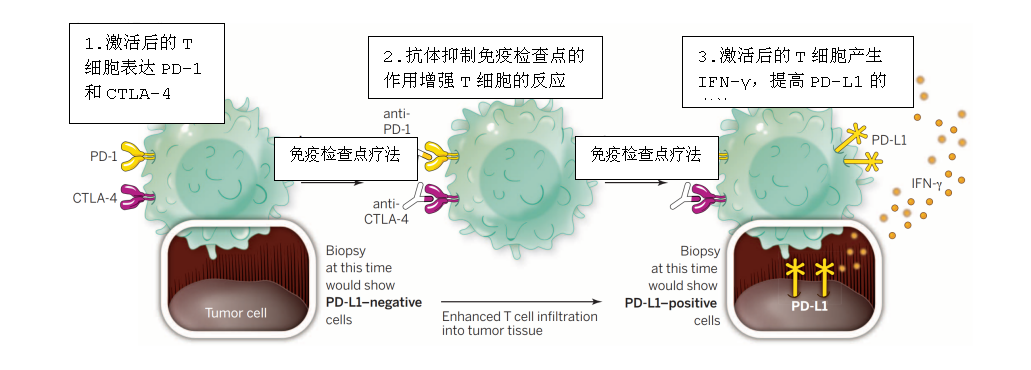

免疫治療,尤其是免疫檢查點抑制劑治療,可以有效恢復T細胞消滅癌細胞的能力,從而給患者帶來顯著和持續的臨床反應。不過,越來越多的研究證明,僅有一部分患者能從治療中獲益,大部分患者對這種療法還是不響應。

免疫治療示意圖

免疫治療示意圖